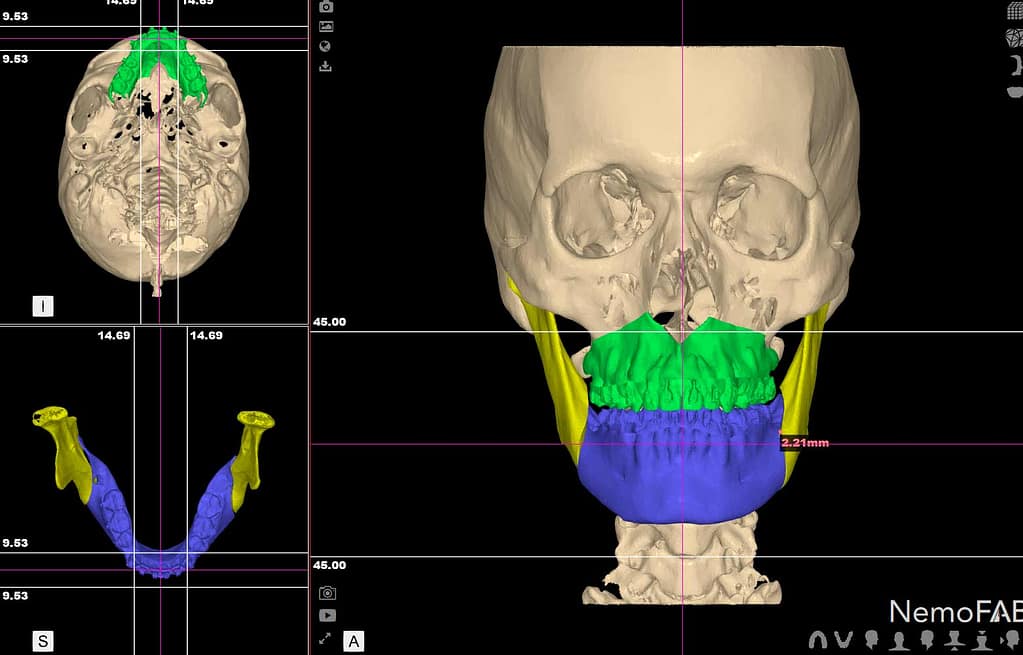

Las Zonas de Seguridad son aquellos límites anatómicos críticos que un cirujano debe identificar y proteger a través de un diagnóstico tridimensional (usando la Tomografía Computarizada de Haz Cónico o CBCT).

- La Zona de Seguridad: Debemos mantener siempre un margen de seguridad de al menos 2 mm entre la punta del implante y el techo del conducto del NDI. Esta distancia se mide con precisión en la CBCT, asegurando que el implante quede por encima del nervio.

- La Zona de Seguridad: Se evita colocar implantes en la proximidad o la trayectoria de este agujero. Es vital identificar su posición exacta, ya que varía entre pacientes, especialmente después de años de pérdida ósea.

La única forma de garantizar el respeto absoluto por estas Zonas de Seguridad es mediante la Planificación Quirúrgica Digital. En nuestra clínica, la CBCT y el software de planificación 3D nos permiten:

- Mapear con precisión la ubicación tridimensional de nervios y senos.

- Determinar la longitud y el diámetro exactos del implante antes de la cirugía.